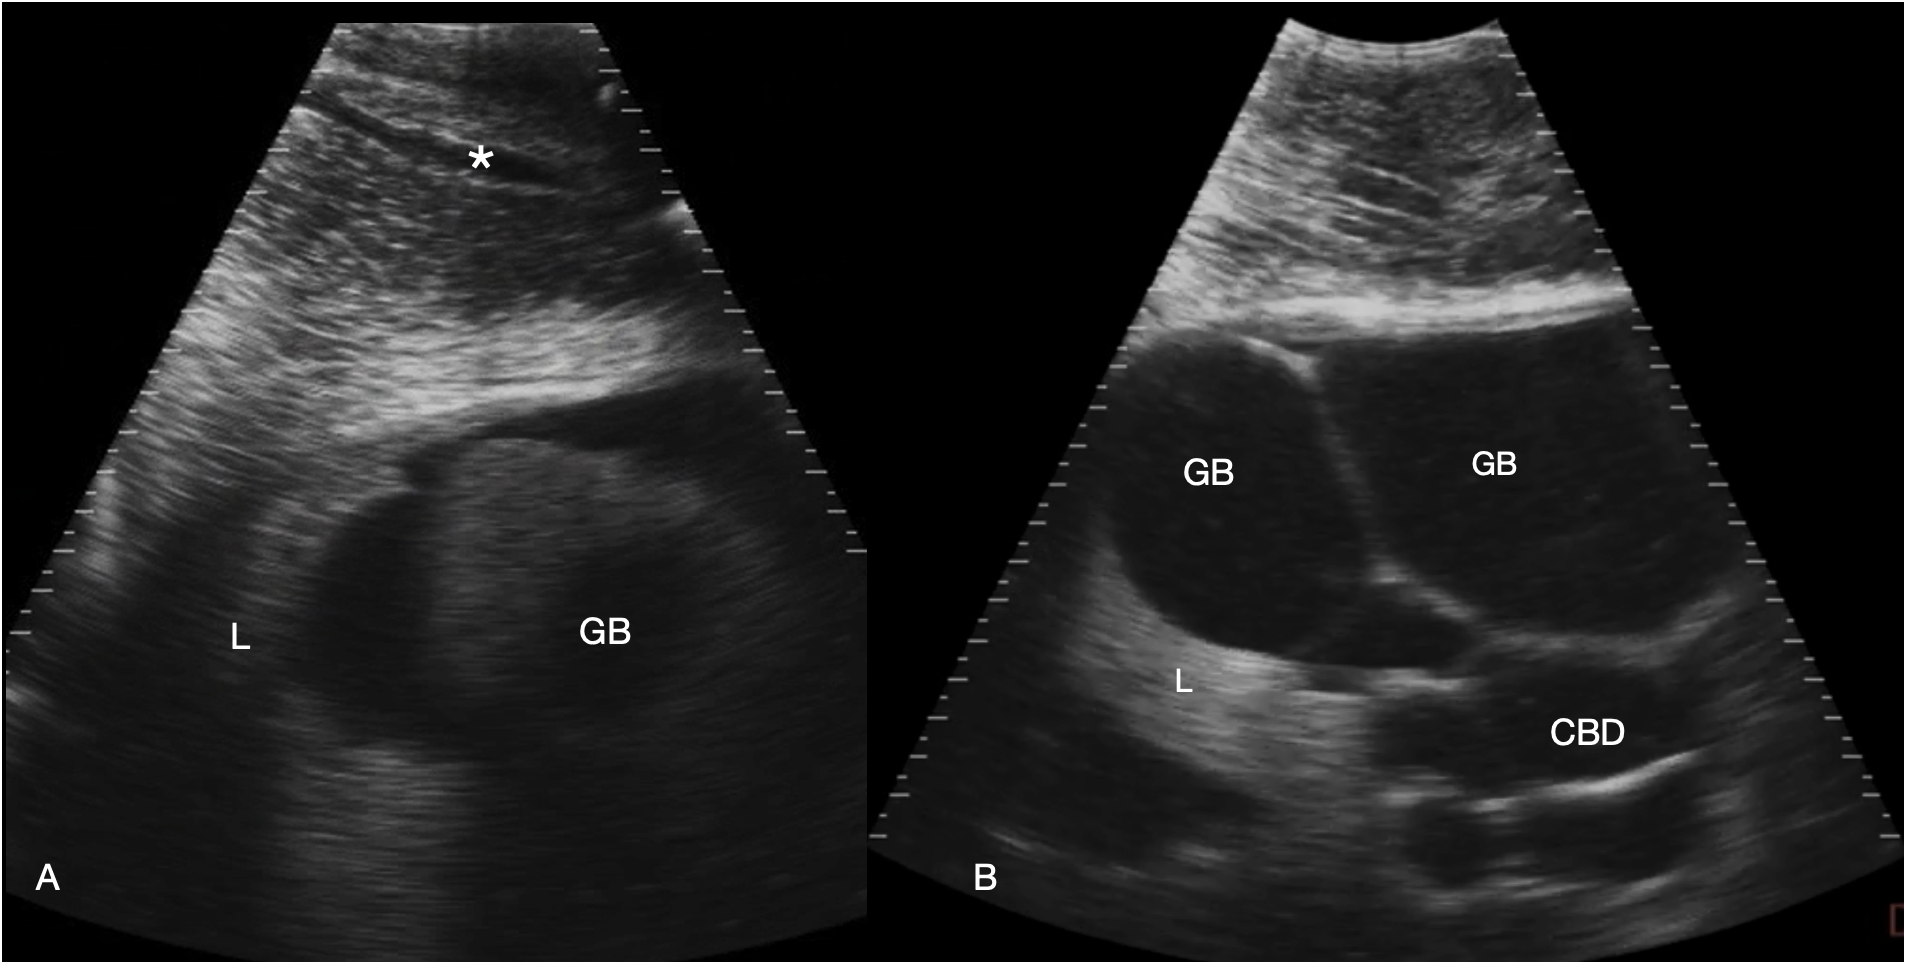

Figure 4

Gallbladder and bile duct. Sagittal sonograms caudal to the pectoral line, display depth 21 cm. Images are displayed with cranial to the left. (A) Right parasagittal sonogram Shark 31. In the abdominal wall a tubular anechoic vein is visible (*). The gallbladder is small and imaged poorly adjacent to the liver. (B) Midline sagittal sonogram, just caudal to the pectoral line in Shark 34. The gallbladder is distended and folded in the near field and the common bile duct and possibly portal vessels in folded tubes in the far field. Some liver parenchyma is to the left of the image (cranial). See Supplementary Video S3.

The liver was recognized by its characteristic shape and sonographic appearance of finely granular parenchymal texture that was generally hyperechoic, becoming hyperattenuating in some individuals. This is consistent with hepatic sonographic appearance in other species with increasing lipid content causing attenuation of the ultrasound beam (Mattoon et al., 2020). The liver was visible from the pectoral girdle to a point caudal to the pelvic fins. The entire liver was not imaged in each animal due to limitations of access and compliance. At the cranial extent there were curved, convex margins that conformed to the transverse septum surface (Figure 3). The lobes were separated by a moderate volume of nearly anechoic peritoneal fluid. In the cranial portion, the lobar margins were triangular in transverse section, with slightly rounded margins. In the mid and caudal abdomen, the liver was positioned in the dorsolateral cavity and was seen as a strap-like, smoothly marginated structure with some occasional internal, tubular anechoic structures (venous sinus likely but not confirmed). The gallbladder was identified on and just to the right of midline, immediately caudal to the pectoral girdle (Figure 4). It was a large, elongated oval structure with a thin wall and anechoic fluid contents. When distended (up to 7.5 cm diameter), it folded on itself and was separated from the adjacent liver by anechoic peritoneal fluid. Dorsal and caudal to the gallbladder a broad tubular structure 2 – 3.5 cm in diameter was identified, coursing caudally in the sagittal plane, consistent with the common bile duct. Dorsal to the gallbladder was a cluster of thin-walled, fluid filled tubes. These may be tortuous bile duct or hepatic portal vascular structures, or a combination of both.